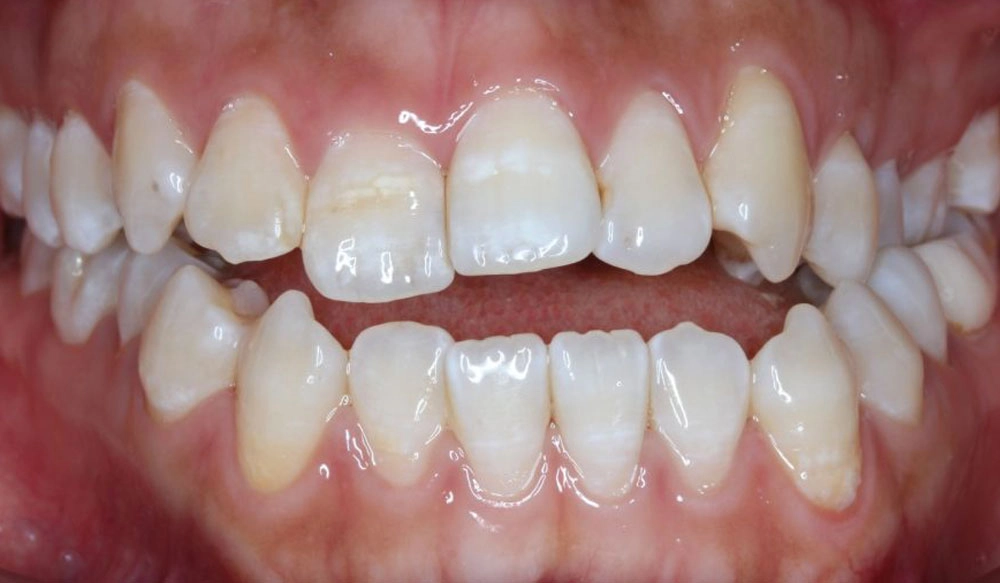

Extraction

Extraction is the removal of one or more teeth when a large amount of space needs to be created to align and create a correct occlusal relationship between the remaining teeth.

Patient Information:

Age: 16

Gender: Female

Invisalign Treatment Option: Invisalign Comprehensive

Total Treatment Time:

16 months